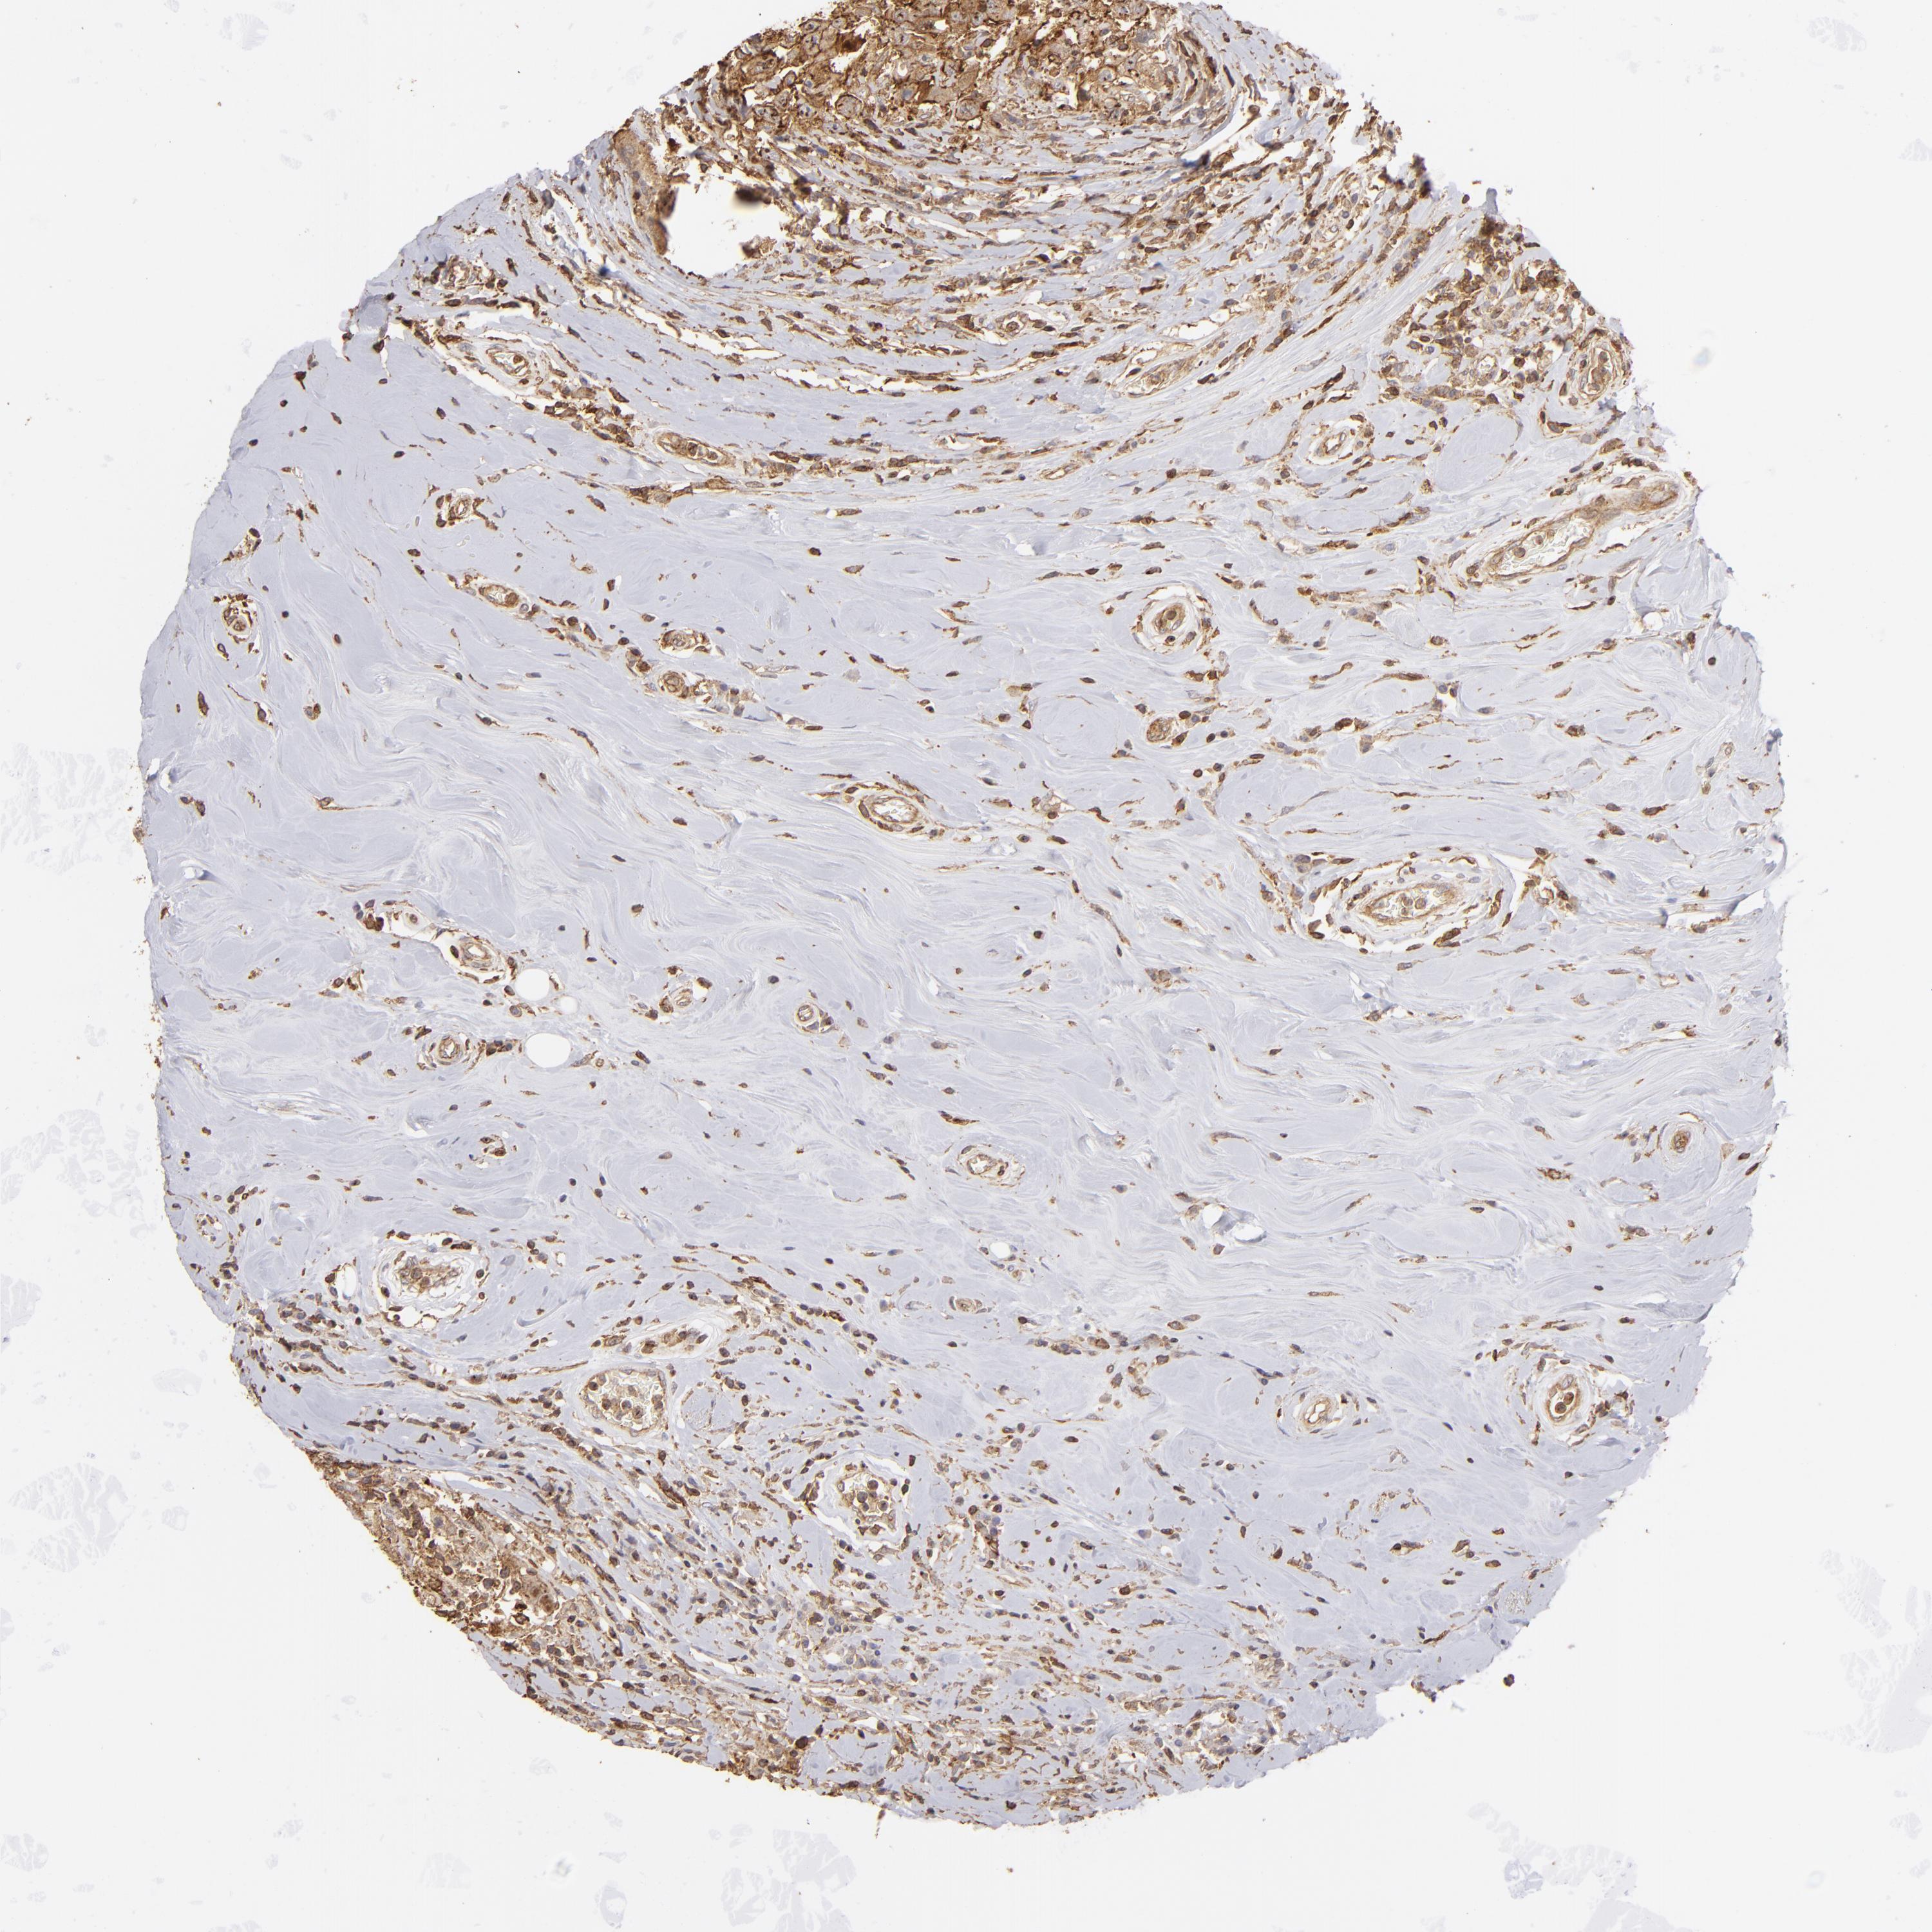

BRCA TCGA BRCA VALIDATION PROTEIN EXPRESSION

ANTIBODIES

AND

VALIDATION